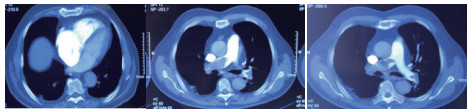

例2 72岁,男性。主因“活动后气短3 d,加重伴有晕厥1次”住院。既往体健,否认制动史及手术史。入院查体:神志清楚,体温36℃,血压120/70 mmHg,脉搏110次/min,呼吸22次/min,脉氧93%(安静,空气氧),轻度乏氧征。双肺呼吸音清,未闻及干湿性啰音。心率110次/min,心律齐,P2 > A2,心界无扩大,无杂音。腹软,无压痛,肠鸣音正常,双下肢无浮肿。神经系统查体未见异常。血气分析(安静,空气氧)提示pH 7.457,PaCO2 26.7 mmHg,PaO2 74.0 mmHg,SaO2 95.5%;D-Dimer 13 743 ng/ml;FDP 175.060 μg/mL,FBG 1.990 g/L;PLT:224 G/L;cTnI 0.04 ng/mL,BNP 666 pg /mL;ALT 15 U/L,AST 27 U/L,CREA 103.3 mmol/L,血Na+、K+、Cl-:正常范围;UCG提示:右心增大,肺动脉主干增宽(28 mm),三尖瓣反流(中-重度),反流面积11.5 cm2,TI法估计SPAP为50 mmHg、左室舒末内径38 mm、左心功能稍减低E波/A波= 60/40 cm/s,未见节段性室壁运动障碍;双下肢静脉超声提示右侧股总、股深、股浅、腘静脉及双侧小腿肌间静脉丛血栓形成。心电图(图 5所示)提示窦性心动过速;CTPA提示双肺主干明确充盈缺损(图 6所示)。入院诊断:急性PE(中高危)。给予低分子肝素重叠华法令抗凝治疗。D-Dimer由入院时13 743 ng/mL分别降至第2天10 000 ng/mL,第3天9 000 ng/mL和第四天的5 000 ng/mL。住院第4天开始出现纳差、恶心未吐,复查心电图提示窦性心动过速,SⅠQⅢTⅢ,胸导T波加深(如图 7所示)。入院第5天床上排便后出现呼吸急促,储氧面罩吸氧(Flow 10 L/min)维持氧合78%(当天INR 2.02),15 min后出现血压、心率下降至消失,心外按压始终无自主呼吸及心律恢复,因家属放弃系统溶栓治疗,抢救2 h无效宣告患者临床死亡。回顾入院后连续复查的心电图提示右心负荷有逐渐加重及胸前导联缺血加重的倾向;UCG同样证实右心室内径呈进行性增大的趋势(分别为入院时的右心房31 mm×47 mm、第2天28 mm×40 mm和第4天的54 mm×60 mm)。

| 图 6 入院时CTPA提示双肺主干明确充盈缺损 |